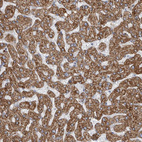

Immunohistochemistry analysis in human kidney and skeletal muscle tissues using HPA026077 antibody. Corresponding GATM RNA-seq data are presented for the same tissues.